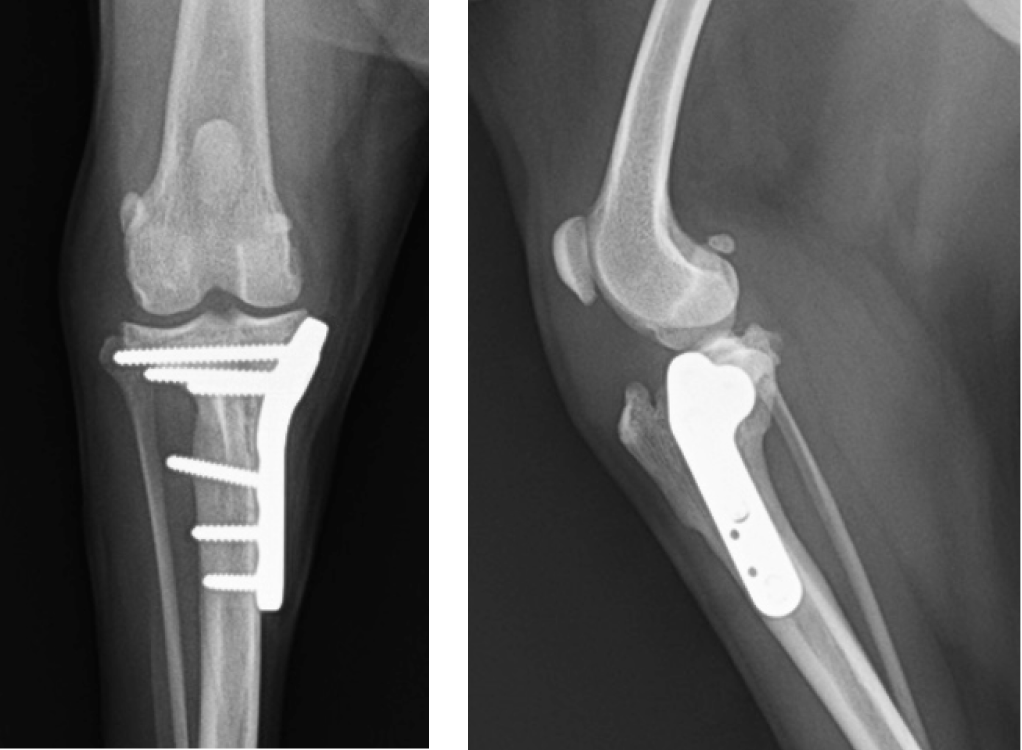

前十字靭帯は大腿骨と脛骨を結ぶ靱帯で、膝の安定性に関連します。この靱帯が損傷することで膝が不安定となり、患肢に体重をかけることができなくなります。原因として前十字靭帯の変性、加齢、外傷によるものがあります。症状は急性で顕著な跛行、痛み、おすわりの時にあしを投げ出すなどです。関節炎の進行や、半月板損傷の合併症が起こります。

治療は、保存療法としての内科治療と人工靭帯を使う関節外法、脛骨を切り大腿骨に対する角度を調整するTPLOなどの外科治療があります。

担当医は、長年大学病院の獣医整形外科専科研修に参加しています。その経験を生かし、当院では前十字靭帯損傷のTPLO、膝蓋骨脱臼整復術、大腿骨頭整復処置、大腿骨頭切除術、骨折など様々な疾患に対応しています。